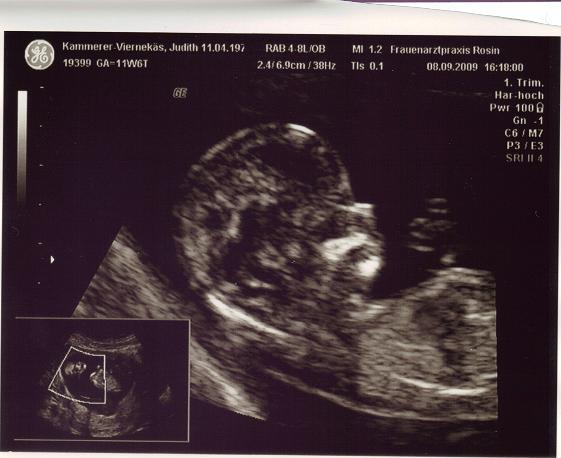

DANKE! Hab noch eines bekommen, vom Kopf

Bild zu

Ohhhhh das sind ja richtig schöne Bilder ................freut mich das alles i.o. ist

Wow.warum kriegt ihr diese 3 oder 4 D Bilder? Bin froh wenn meine Zwerge auf Sono nicht grad nach Alien aussehen. Brauch glaub neuen Arzt.

Hi! Mein Arzt hat da so n schönes Angebot ... Babyfernsehn bei jedem Besuch ... kostet 130 €. Und wenn ich im Krankenhaus in unserer Stadt entbinde, bekomme ich 80 € erstattet. Finde das ist ne feine Sache LG Judith